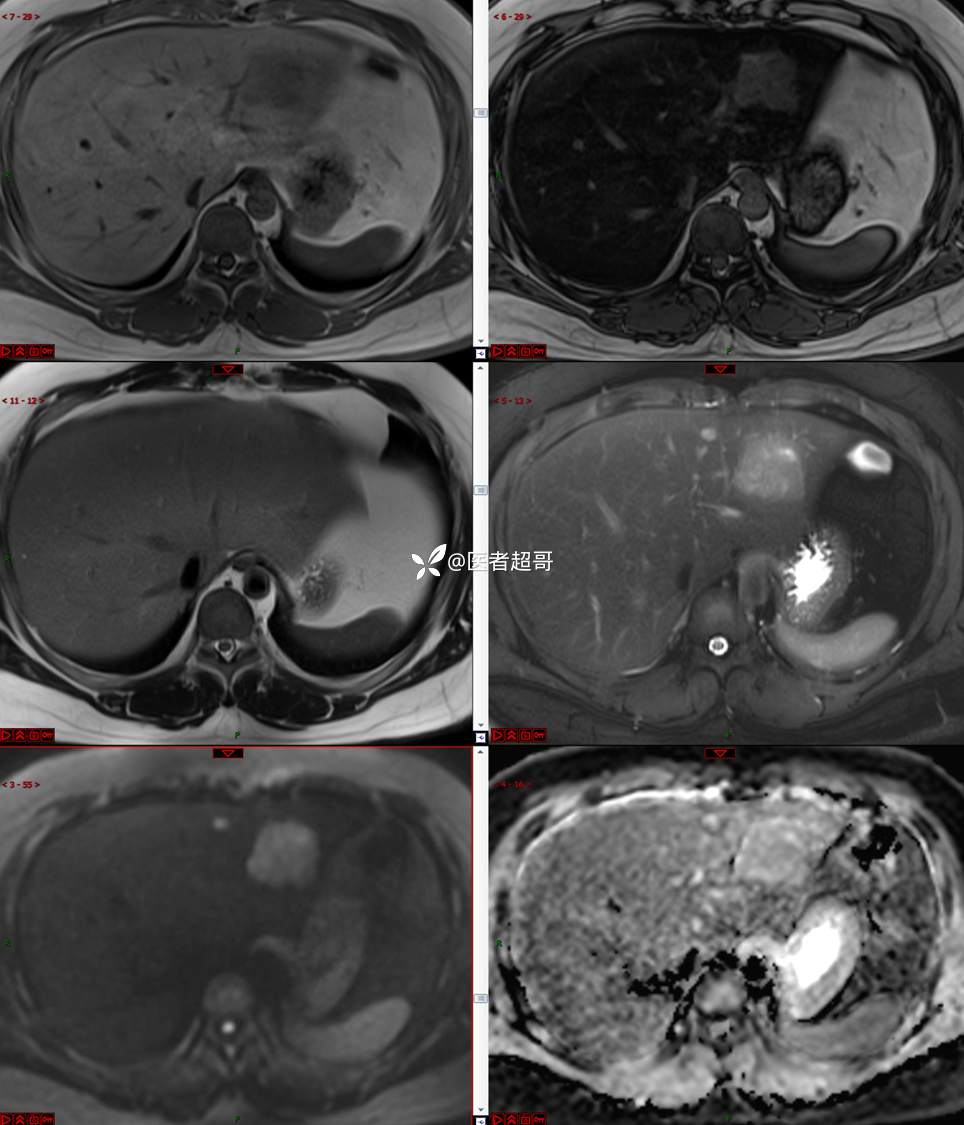

【影诊笔记685】男,31y,发现肝占位性病变5天就诊,请诊断分析,有病理结果!

主 诉:发现肝占位性病变5天。

现病史:患者缘于5天前体检时发现肝占位性病变,未予以特殊处置。现患者为求系统诊治就诊于我院,行普美显提示:肝左叶富血供占位,请结合临床及其他检查,肝多发血管瘤,脂肪肝,肝囊肿,请结合临床。门诊以“肝占位性病变”收入我科。病程中,饮食睡眠可,二便可,近期体重未见明显变化。